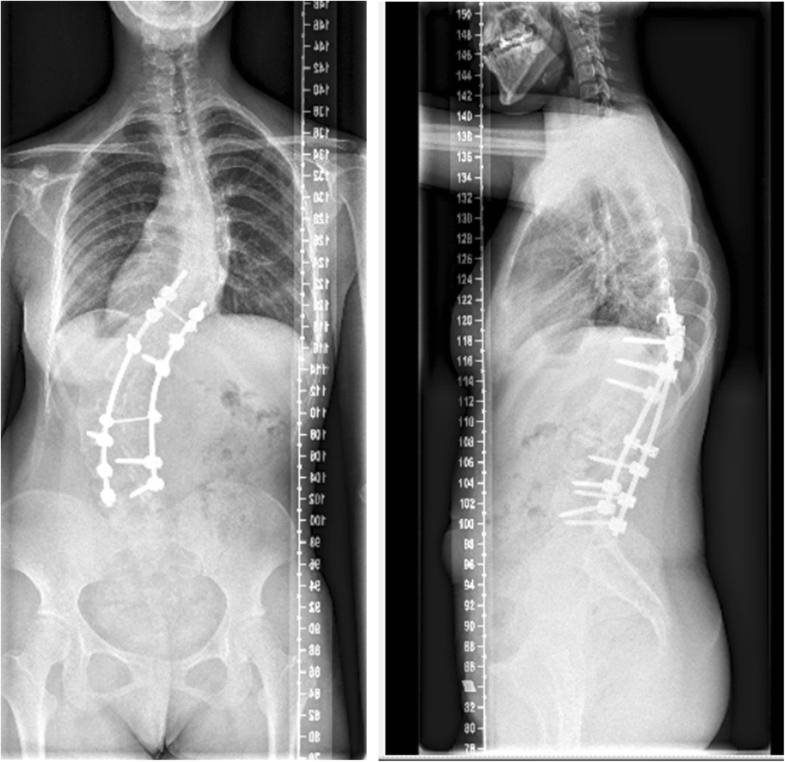

Kyphoscoliosis literature review image This image illustrates kyphoscoliosis literature review.